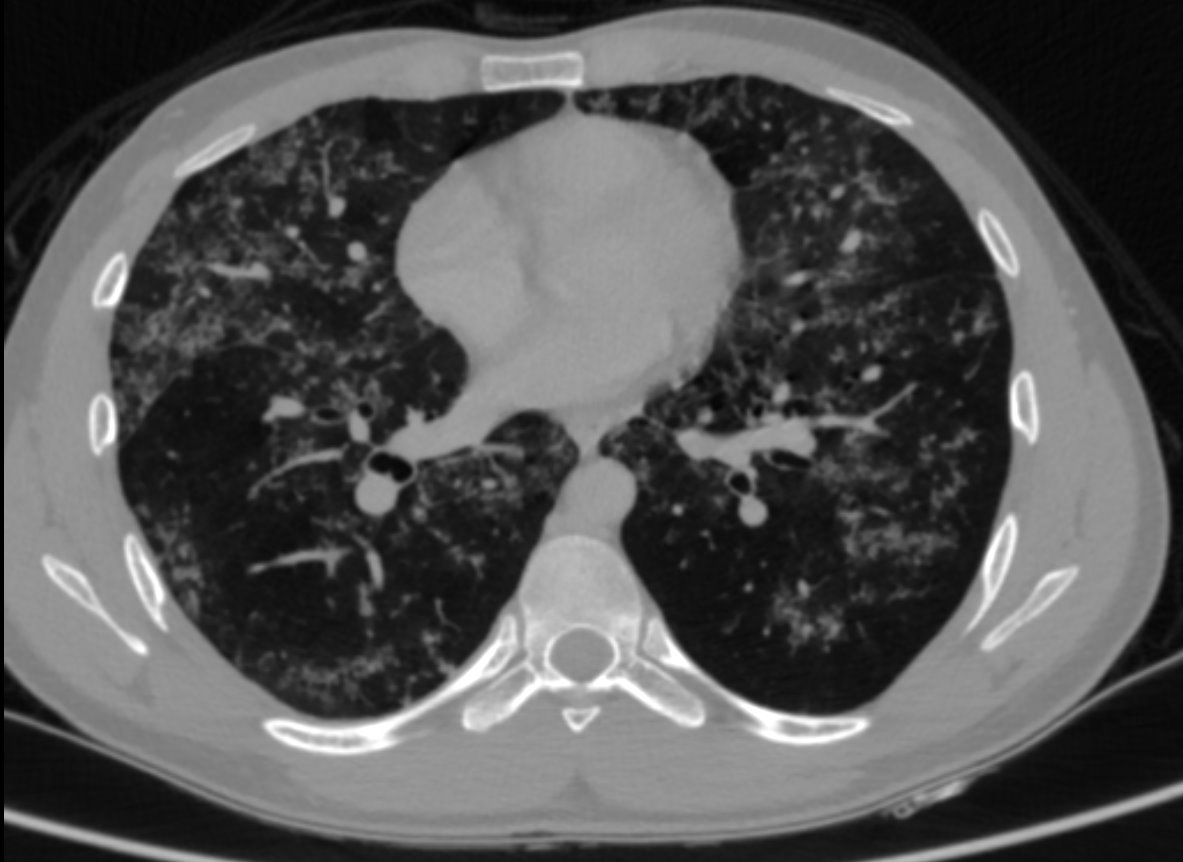

• HRCT thorax was performed.

• Numerous patchy nodular parenchymal infiltrates distributed diffusely in all the lung lobes, with a peribronchovascular and subpleural distribution.

• Apical emphysematous changes.

• No significant mediastinal lymphadenopathy seen. No effusion

• Alveolar sarcoidosis